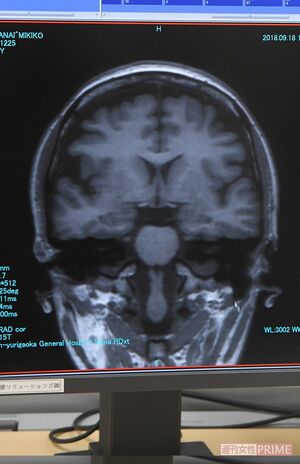

その後、MRI検査へ。検査技師に「金属は身につけていませんか?」「閉所恐怖症ではありませんか?」と確認され、耳栓を装着してから、検査台に横たわりドーム状の検査機の中へ。検査が開始されると、耳栓をしていてもかなりの音量で「ビービービー」「ゴトゴトゴト」と工事現場のような音が聞こえてきた。